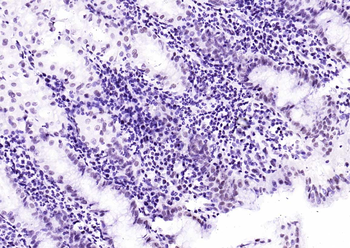

100 μl, 50 μl, 25 μl - Rad51 Recombinant Rabbit Monoclonal Antibody [orb608069]Featured